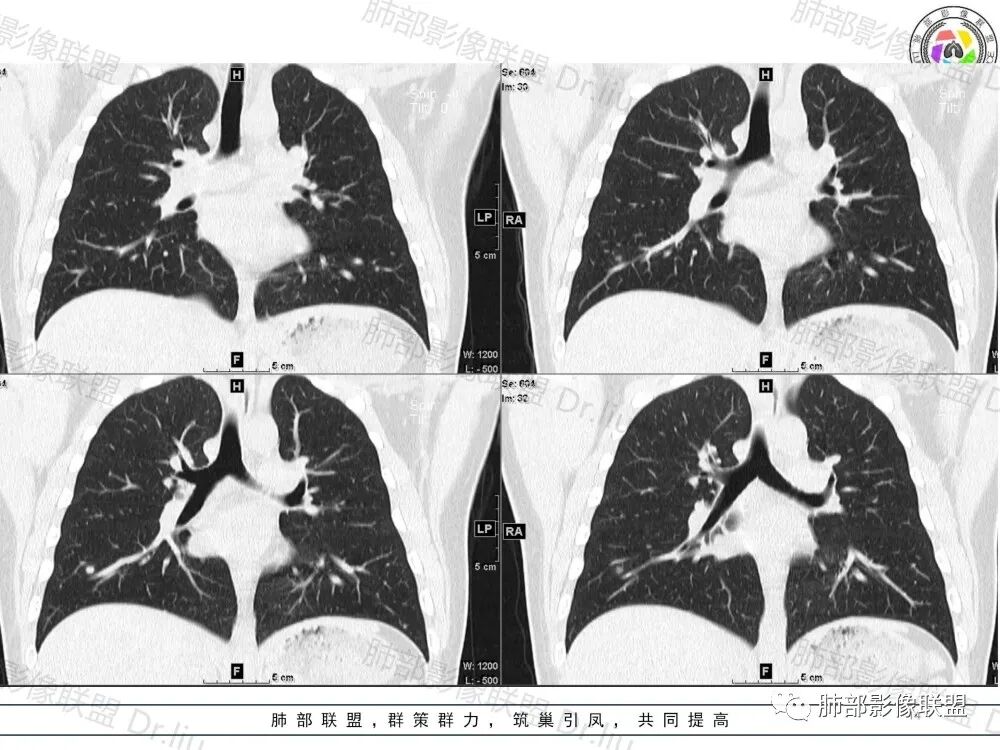

2、影像特点:两肺可见多发大小不一的结节影,部分结节周围可见晕征,部分结节沿着支气管血管束分布,部分位于胸膜下。前纵隔内可见多发结节样软组织密度影,边界不清,部分病灶融合倾向,其脂肪间隙显示模糊。由于腹腔层面少,未能确定腹腔内有无增大淋巴结,需要连续层面追踪观察。

3、病例小结:年轻男性+前纵隔多发结节样软组织影+双肺多发结节,需要警惕淋巴瘤,至于多数老师提到鉴别结节病,结节病以双肺门对称性淋巴结肿大为典型表现,其肺内表现多为沿肺门旁支气管血管周围间质分布的多发结节,结节病可表现纵隔内多发淋巴结肿大、且淋巴结密实,孤立少融合,该病例中均缺乏以上特点,另外结节病好发中青年女性,此病例年龄亦不符合。